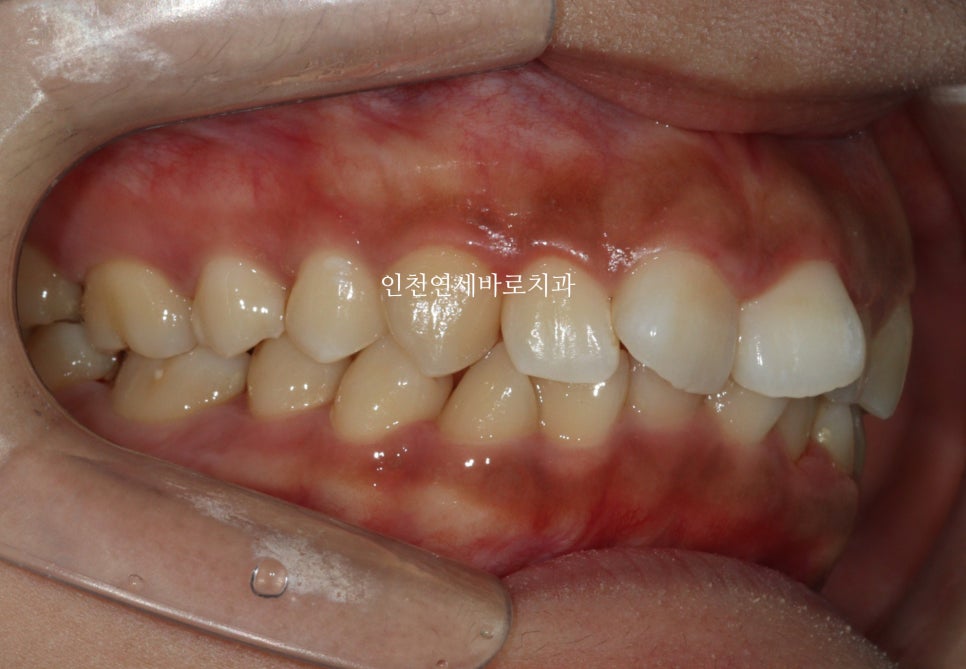

시작 후 약 4-5달 후 사진입니다.

위 사진이 7월에 재제작 했을 때 모습입니다.